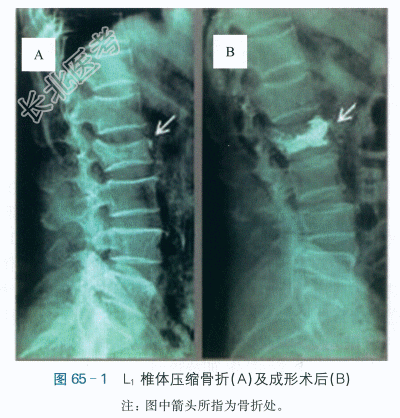

患者,女性,69岁,因“腰2椎体压缩骨折成形术后1天”康复早期介入治疗。患者4天前不慎跌坐地上,伤及腰背部,自觉疼痛,无法站立,遂至医院急诊,X线片提示L₂椎体压缩性骨折,如图65-1A所示。于次日在局麻下行腰椎椎体成形术。患者术后神清,腰部疼痛,表情痛苦,饮食及二便正常。目前腰部酸痛,活动度下降,康复早期介入治疗。

血常规:WBC6.6×10⁹/L,GR74.8%,RBC4×10¹²/L,Hb120g/L,PLt164×10⁹/L。凝血功能:PT13s,PTA78.3%,APTT26.3s。血钾4mmol/L,血钠143mmol/L,血氯107mmol/L。术后X线片示L₂椎体压缩骨折术后改变,椎体高度部分恢复,如图65-1B所示。